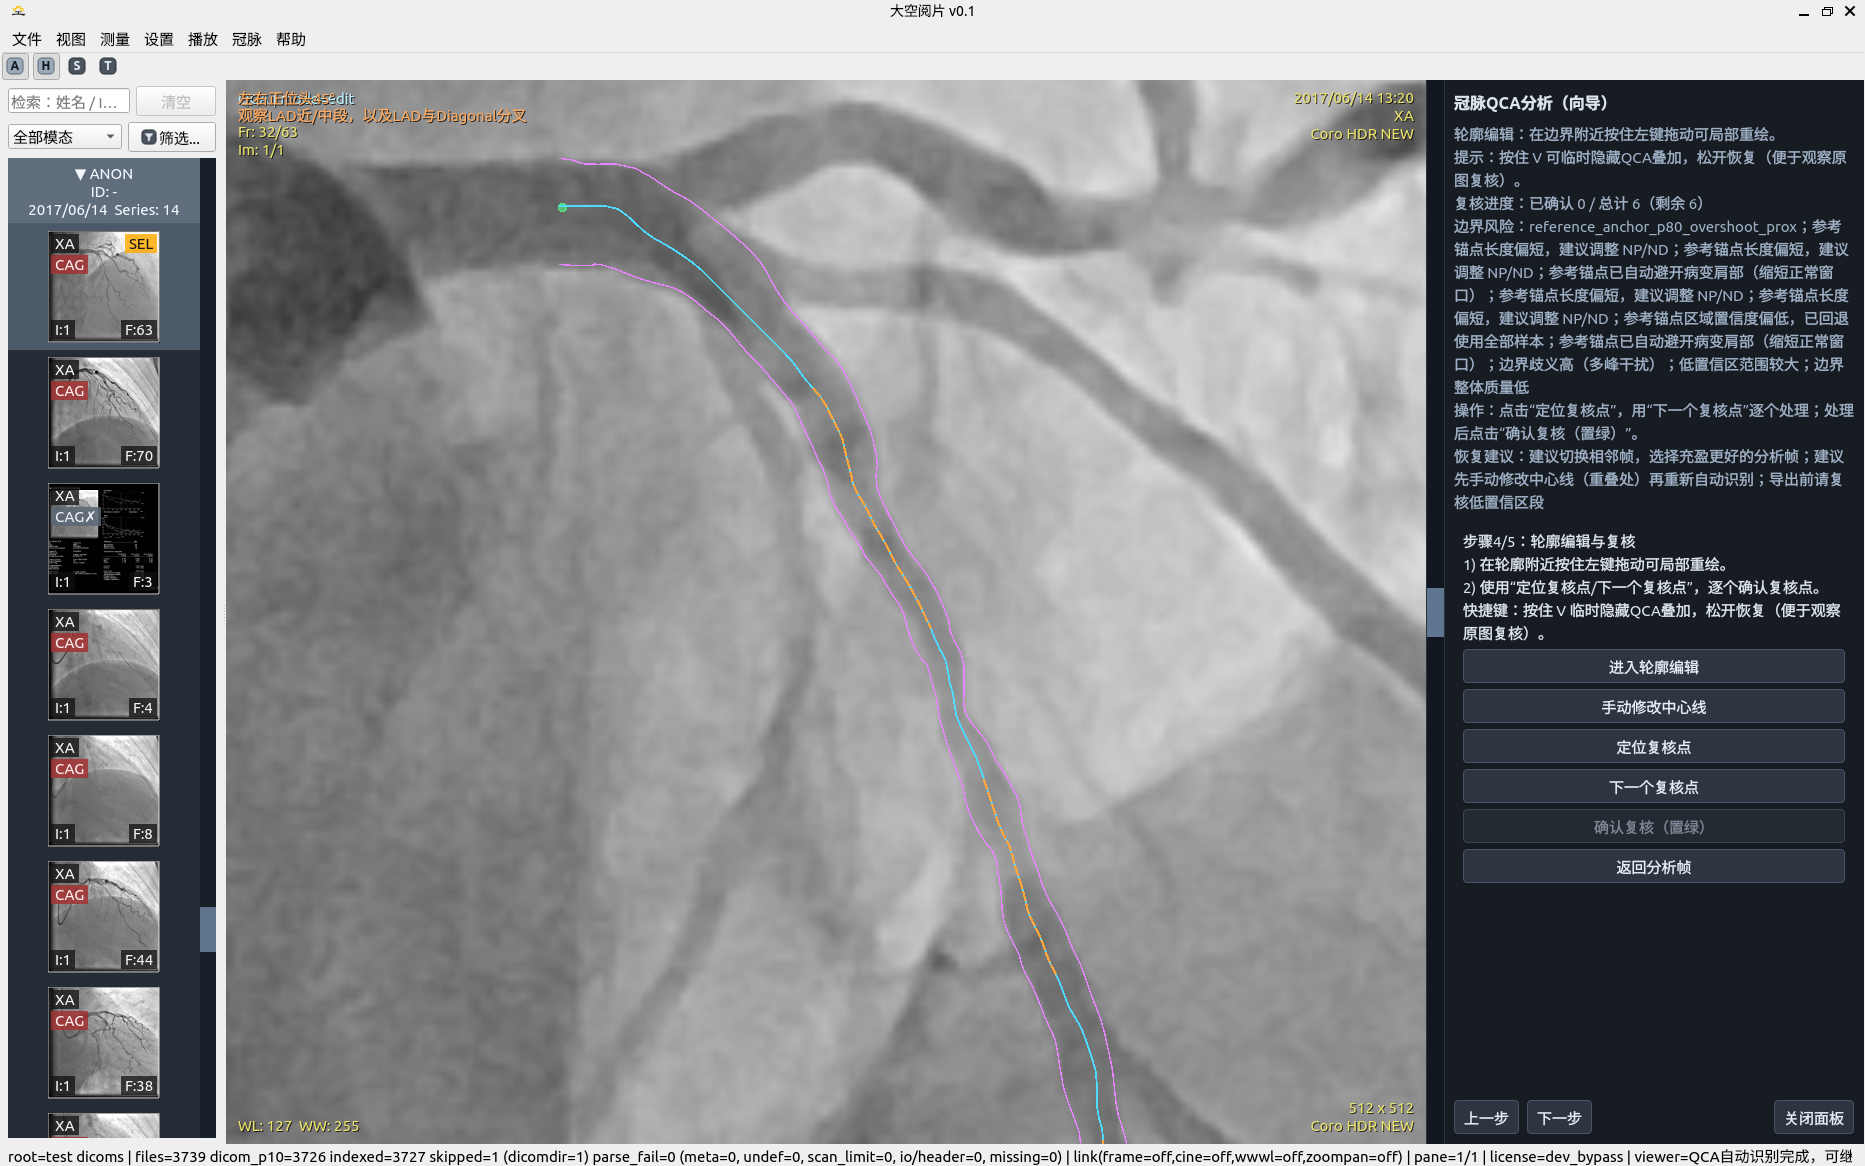

5. 冠脉 QCA 分析

半自动流程强调“可解释 + 可修正 + 可重算”,而非一次性黑盒输出。

• 导管标定:拉直空间剖面 + 左右联合动态规划(DP)+ 亚像素修正。

• 边缘检测:极性自适应 + 有符号边缘特征 + 联合状态 DP + 多峰歧义度。

• 稳健性:MAD 统计、质量等级、结构化告警与恢复建议。

• 几何交叉校验:SID/SOD/ERMF/像素间距参与比例复核。

移动端请按步骤顺序阅读:步骤 1 → 步骤 7。

中心线与血管轮廓自动识别

QCA 分析步骤 5

血管轮廓修改及自动复核位置提示